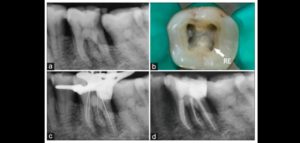

132 – Tratamiento de la reabsorción radicular interna idiopática perforante: controles radiográficos

La reabsorción radicular interna (RRI) es una afección inflamatoria que resulta en la destrucción progresiva de la dentina intra-radicular a lo largo de los tercios